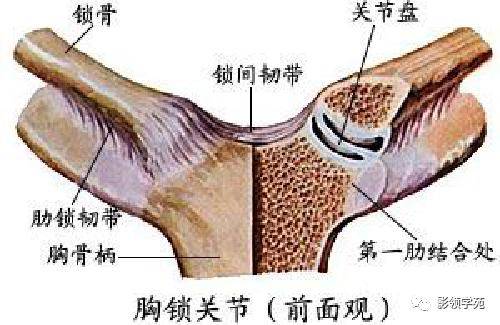

关节与韧带系统

关节与韧带系统